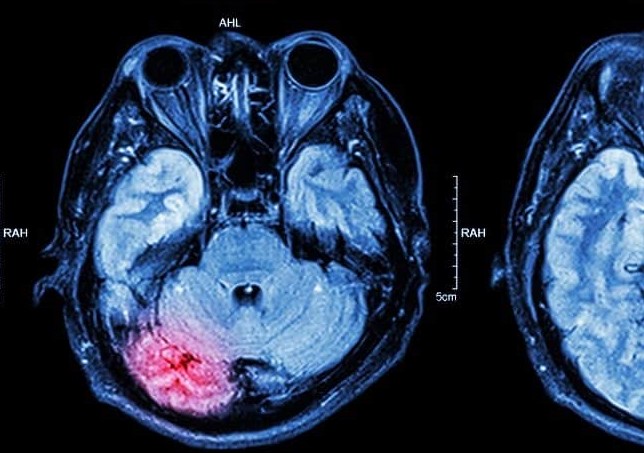

La lesión cerebral traumática (LCT) continúa siendo una de las principales causas de discapacidad prolongada a escala global.

Tras un golpe brusco —derivado de una caída, un accidente de tráfico o una colisión—, el cerebro pone en marcha procesos patológicos como la inflamación, el estrés oxidativo y el daño neuronal, que pueden mantenerse mucho tiempo después del episodio inicial. No obstante, los métodos diagnósticos habituales no siempre detectan la evolución progresiva de estas lesiones, y los tratamientos actuales presentan dificultades para alcanzar con precisión las áreas afectadas.